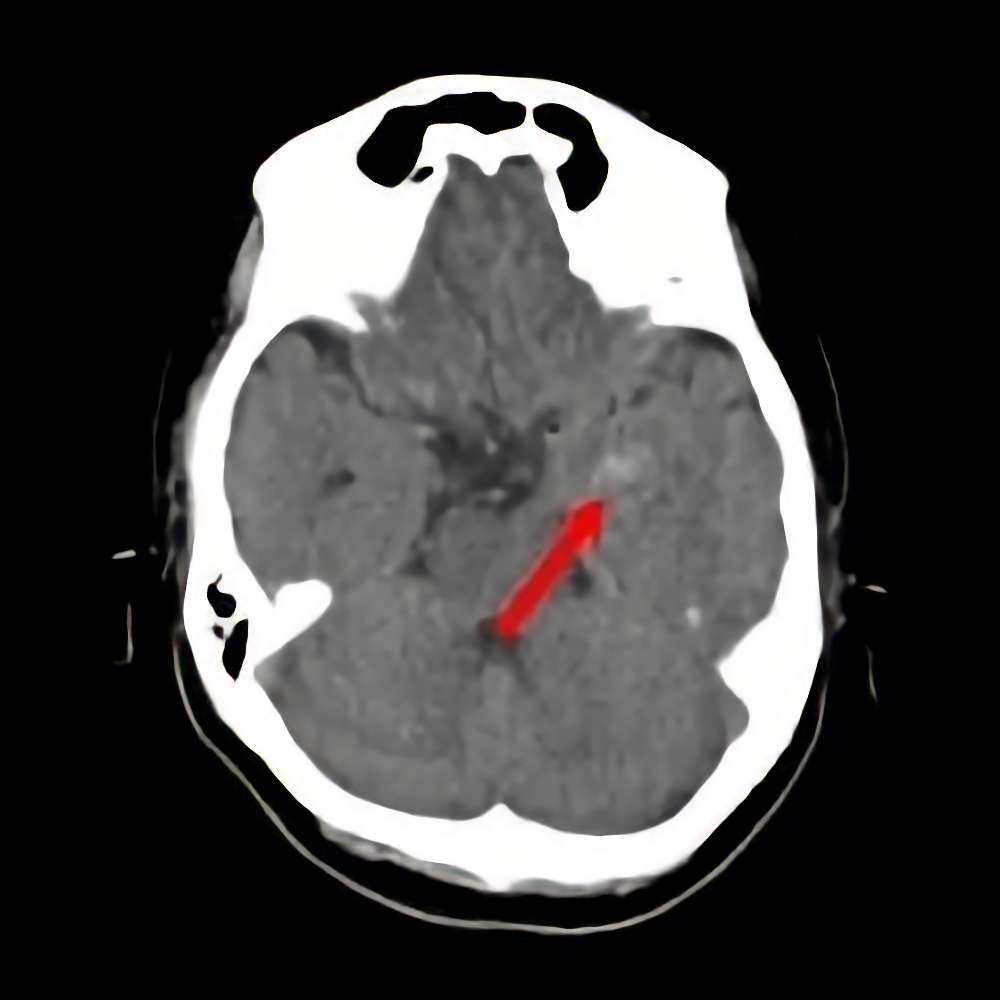

断層撮影

手術前1